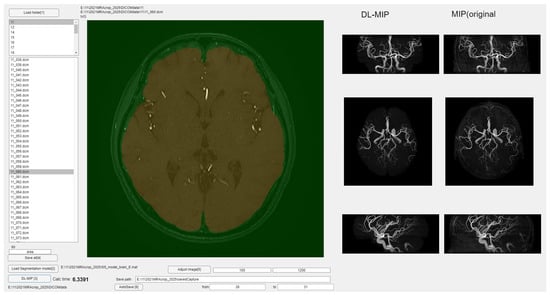

Figure 6 and Figure 7 present the MIP images generated by applying the slice-wise masks shown in Figure 2, Figure 3 and Figure 4 to the 3D volume. After the masks are applied, a MIP is performed on the resulting 3D dataset, providing a final MIP that excludes non-intracranial arteries. When the masks (Figure 2, Figure 3 and Figure 4) accurately preserve only the intracranial arteries, the MIP images (Figure 6 and Figure 7) clearly show reduced interference from external carotid branches and highlight the internal carotid and vertebrobasilar systems. In order to evaluate images produced by the segmentation step, a dedicated software application was developed (Figure 6). This software can load a folder containing DICOM files for axial images acquired by MRA, and upon pressing the “start processing” button, it automatically converts each DICOM file into a JPEG image, applies the segmentation model, and incorporates the resulting mask back into the DICOM data. It then saves a three-dimensional matrix reflecting the applied segmentation, effectively providing an automated workflow from raw images to a fully segmented 3D volume. As a preview, the software displays MIP images viewed in axial, sagittal, and coronal orientations side by side, enabling a direct visual comparison of MIP images without segmentation versus those with segmentation applied. This interface helps verify how effectively undesired regions have been removed.

Figure 7 illustrates a qualitative comparison between the MIP images generated from the original TOF-MRA dataset and those produced after applying the segmentation model. The images processed through the developed software show a significant reduction in non-essential vascular structures, particularly in the external carotid branches. The results indicate that the segmentation model successfully isolates the intracranial arteries while preserving their anatomical integrity, thereby enhancing the clarity of MIP images for diagnostic purposes.

To further evaluate the effectiveness of the trained segmentation model, MIP images were generated based on the segmented outputs. As shown in Figure 6, the automatically processed MIP images exhibited clear suppression of external carotid branches, including the superficial temporal artery and middle meningeal artery, which are commonly misrepresented in conventional TOF-MRA MIP images. However, despite the overall success in removing non-intracranial vessels, certain venous structures, such as the occipital venous sinus, were not entirely excluded in some cases. One potential reason for this incomplete removal is that these veins travel within the brain parenchyma, making their signal intensity distribution more variable and less distinguishable from arteries based on conventional segmentation features. Additionally, the anatomical variability in venous structures across individuals may have introduced inconsistencies in the training dataset, thereby reducing the model’s ability to generalize effectively to all cases.

Figure 6. Overview of the developed software for automated segmentation and MIP image generation.